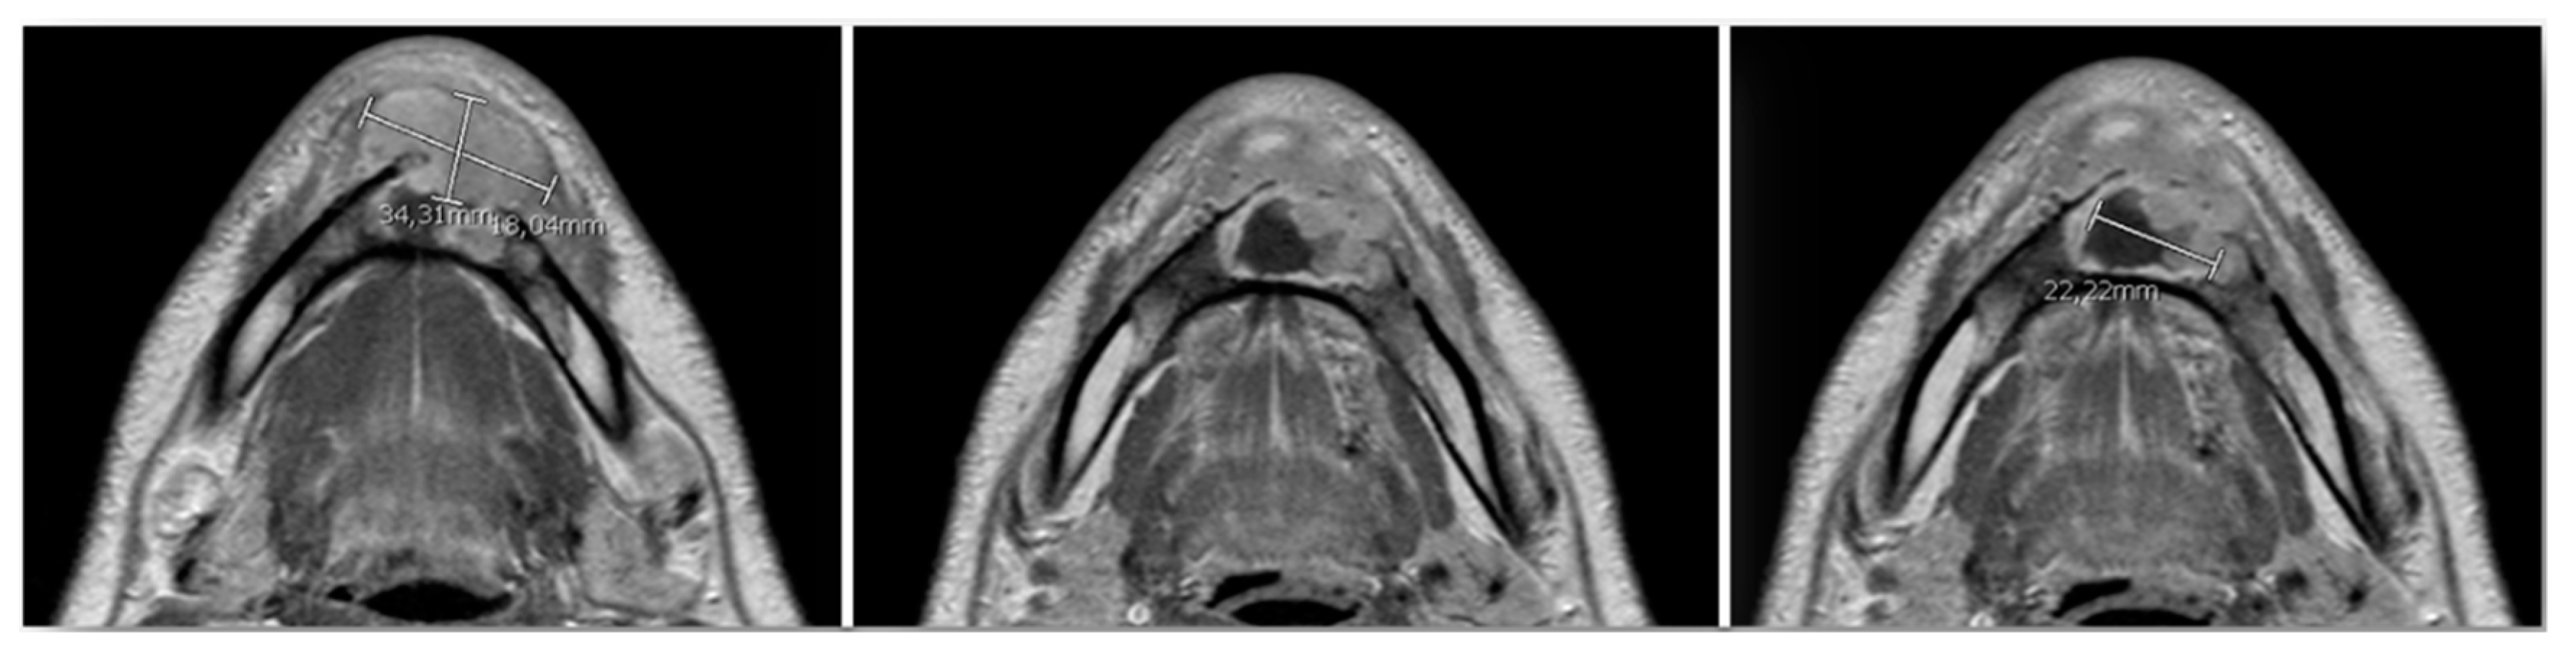

For oncological staging, the patient had orthopantomography, preoperative CT and MRI (Figure 6) of the head and neck, CT of the thorax, all with and without contrast, ultrasound echography of the neck and abdomen, a rhino-pharyngo-laryngeal fibroscopy and an angio-CT of the inferior limbs. No secondary lesions nor lymph node invasion were detected in preoperative staging.

Figure 6.

Preoperative MRI, multiple axial views. Vestibular extraosseous spread of the tumor was evident.

In our case, orthopantomography (Figure 1) and CT (Figure 2) showed a uniloculated 38 × 14 mm osteolytic area affecting the chin symphysis and extending in the left paramedian region. The lesion interrupted the vestibular bone cortex but spared the lingual one.

MRI with gadolinium-contrast represents a second-level examination essential for tumor staging, and in our case, the extent of the lesion through the anterior cortex erosion in the soft tissues of the chin was documented (Figure 6).